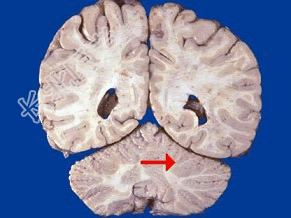

- 单项选择题如图箭头所示,应属于大脑的哪个部位 ( )

A、脑干

B、额叶

C、枕叶

D、小脑

E、顶叶